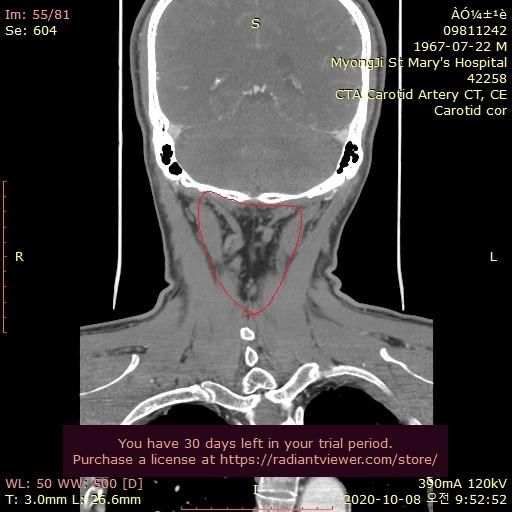

그런데 가까운 의원에서 그때의 영상을 보다가 그림과 같이 목 뒤쪽에 정맥혈관에 기형이 심한것을 알았습니다.

울퉁불퉁 하고 아주 굵어져서 혈액 순환이 안도는것으로 보입니다.

자료 찾아보니 심부경정맥 인것 같습니다. 내경정맥등과 함께 뇌의 혈액을 심장으로 빼내서 보내주는 중요한 혈관으로 보입니다.

기형이 심해서 혈액이 잘 안 빠지는 것일까요?

• 3번 째 사진